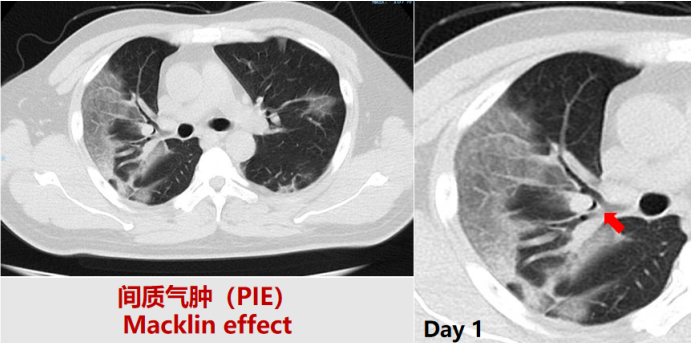

患者,男性,48岁。发热、呼吸困难13天,2022年12月28日入普通病房住院。诊断:新冠肺炎。既往高血压病史14年。经抗感染、抗炎、抗凝治疗后好转。第7天胸部CT提示纵隔气肿+皮下气肿,转入ICU。HFNC 40 L/min,FiO2 0.6,PFR 260 mmHg。予抗病毒、抗感染、激素、抗凝治疗。第21天转出ICU。

图片